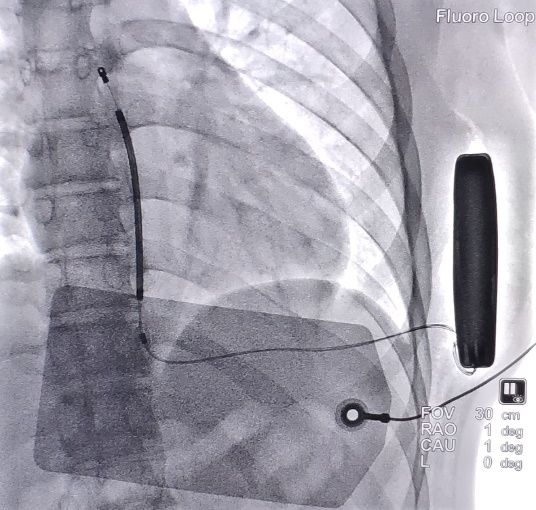

手术在全身麻醉下进行,于左侧第4肋间沿腋中线走形切开皮肤10厘米,逐层分离皮下组织至筋膜层,作囊袋确保足够深度来容纳装置。于剑突下切开皮肤2厘米,逐层分离皮下组织至筋膜层,通过隧道穿引针连接囊袋,再沿胸骨向上约15厘米处切开皮肤1厘米,逐层分离皮下组织至筋膜层,通过隧道穿引针连接剑突下切口,使用隧道穿引针将45厘米长的3401除颤电极从囊袋经隧道送至剑突下切口,固定电极中段,再使用隧道穿引针将电极经隧道送至胸骨上方切口,固定头端。连接脉冲发生器A209,置入囊袋内,以庆大霉素盐水冲洗各术区及囊袋,逐层缝合皮下组织及皮肤,术区纱布覆盖,包扎,弹力绷带加压包扎止血。

术后行诱颤测试,S-ICD正确识别室颤后成功除颤转复为窦律,除颤能量65焦耳,手术圆满成功。术后患者恢复良好。

术后影像